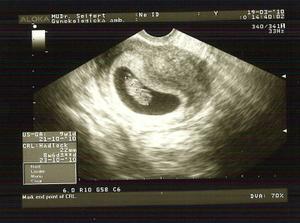

6.3.2010 ráno objevené špinění, ve strachu sedáme do auta směr pohotovost, ale tam jsme uklidněni, miminko je v pořádku, je 0,6 cm velké a tluče mu srdíčko je to nádhera, jsme 6+3tt

19.3.2010 kontrola u gyndr, vše v pořádku podle ultz. jsme 8+6tt a máme 22mm, dnes mimísek poprvé zamával a bylo to úžasné a slyšela jsem jeho srdíčko, je to něco kouzelného, nádherného